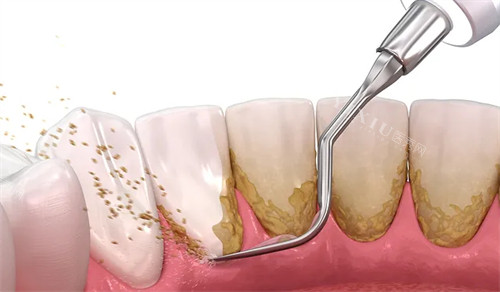

更让洁牙患者惊喜的是超声洁牙仪的"温柔模式"。"以前洁牙像电钻钻头,这里用的是微气泡震动。"刚做完龈下刮治的李女士说,"护士还给我敷了冰镇牙周膜,整个过程像做SPA。"